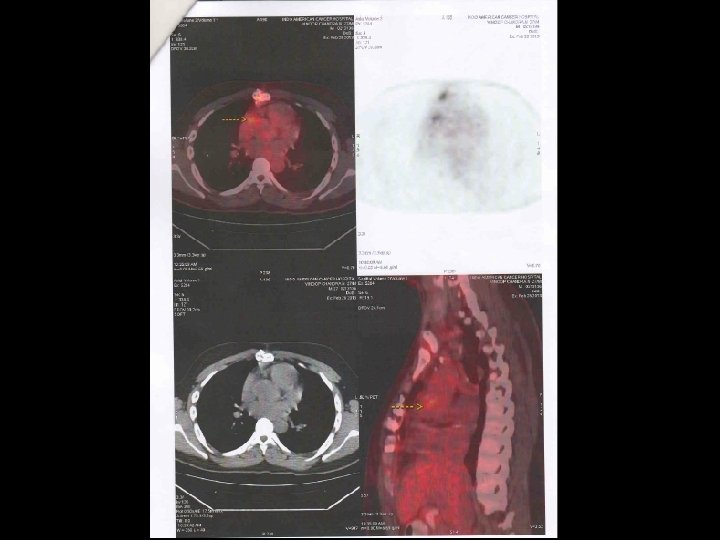

Vinoop Chandra N. 20/3/2013 26 Y/ M Quadricuspid AO Valve AVR (ATS Valve) IE – Immediate Post OP PET FDG + CULTURE STAPH. AUREUS